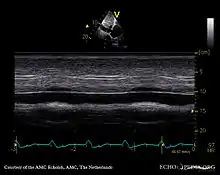

Echocardiography

If pulmonary hypertension is suspected based on the above assessments, echocardiography is performed as the next step.[12][15][56] A meta-analysis of Doppler echocardiography for predicting the results of right heart catheterization reported a sensitivity and specificity of 88% and 56%, respectively.[58] Thus, Doppler echocardiography can suggest the presence of pulmonary hypertension, but right heart catheterization (described below) remains the gold standard for diagnosis of PAH.[12][15] Echocardiography can also help to detect congenital heart disease as a cause of pulmonary hypertension.[12]

- 4-month-old with pulmonary hypertension as seen on ultrasound[59]